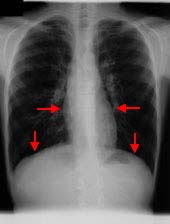

胸部立位正面

このお子さんは頻回に喘息発作が生じていたにも関わらず、民間療法にて長い間治療をされていました。

喘息により肺の含気が多くなり、肺野は明るく(写真では黒く)抜けて見え、横隔膜の位置も下がり、心臓は肺に圧迫されて長細い「滴状心」と言われる形になっています。